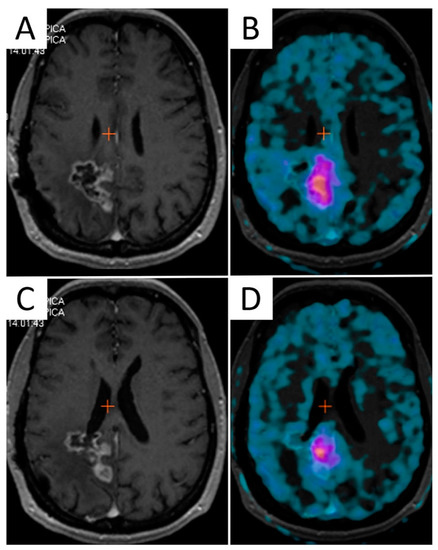

Amino acid PET has shown better accuracy than standard MRI in the definition of brain tumor extent [28], and its inclusion in the surgical planning demonstrated a positive impact on survival [29]. Additionally, the biological tumor volume (BTV) identified by amino acid PET demonstrated a significant prognostic value either after surgery [30] or after postoperative chemo/radiotherapy in GBM. These findings provide a strong rationale for the incorporation of amino acid PET in RT planning [31] (Figure 1).

Figure 1. The mismatch between contrast-enhanced T1-weighted MRI and 3,4-dihydroxy-6-[18F]fluoro-L-phenylalanine (F-DOPA) PET/CT in a 45-year-old female patient with recurrent GBM after multimodal first-line therapy. Two axial contrast-enhanced T1-weighted images (A,C) along with corresponding F-DOPA PET/CT slices (B,D) identifying different volumes of disease.